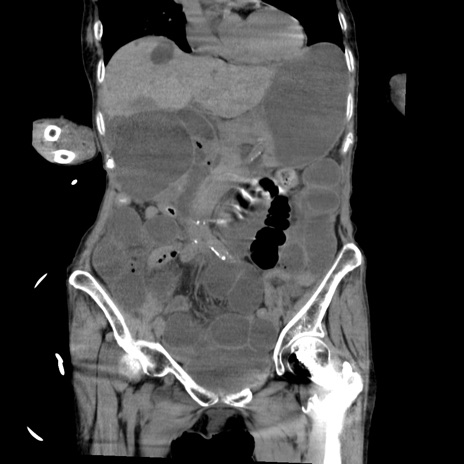

症例27(冠状断像)

【症例】80歳代女性

【主訴】嘔吐、腹痛

【現病歴】数時間前より嘔吐あり。心窩部痛出現し、徐々に右下腹痛あり。その後も数回嘔吐あり救急搬送となる。

【身体所見】腹部は膨隆しているが軟らかく圧痛なし。腸雑音はやや亢進。

【データ】WBC 12000、CRP 19.05